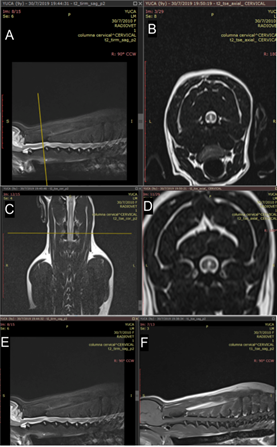

Se realizo una resonancia magnética (RM) de la medula espinal cervical sin contraste en diversos planos ponderadas en T1-W (sagital, dorsal y transversal) y T2-W (sagital, dorsal y transversal). Entre los hallazgos se encontró lesiones hiperintensas en varios segmentos cervicales, también se observa una zona con hiperintensidad con aumento del diámetro del conducto ependimario a nivel medular en el corte transversal, sagital y coronal (Figura 1), en C2-C3 y C4 de la RM ponderada en T2, compatible con siringohidromielia. Cuerpos vertebrales y discos intervertebrales normales. En cuanto a los signos clínicos es importante mencionar que del dolor paravertebral cervical siguió un deterioro neurológico rápido pese a que el tratamiento con corticoides se empezó inmediatamentes. Es probable que la respuesta a estos no fue tan eficiente al tratarce de una AMSR crónica, las mismas que se recomienda que sean medicadas con otros inmunosupresores, debido a esto se uso para el tratamiento citarabina. El protocolo que generalmente se usa es prednisolona 2mg/kg cada 12 horas por 2 días, después 1mg/kg cada 12 horas por 12 días, si hay mejoría clínica se puede disminuir la dosis cada 6 semanas durante 24 semanas, pero estos fármacos pueden causar efectos adversos que incluso llegan a ser el motivo de eutanasia (Giraud et al., 2021), en este caso el paciente se trató además con citarabina que ha sido reportada como una opción de tratamiento váliday bien tolerada en casos de recaídas de AMSR (Günther et al., 2020).

La resonancia magnética presentó siringohidromielia cervical, la siringohidromielia puede ser producida por cualquier patología que curse con obstrucción de LCR (epidimitis, meningoencefalomielitis, malformación de Chiari y neoplasias). Se describe asimismo como otra posible causa de siringohidromielia a las enfermedades inflamatorias del SNC (Portero, 2018). De igual importancia en la resonancia magnética T2-W se encontró lesiones hiperintensas en varios segmentos cervicales a nivel medular en el corte transversal de T2-W., estos hallazgos fueron sugerentes a una lesión inflamatoria.